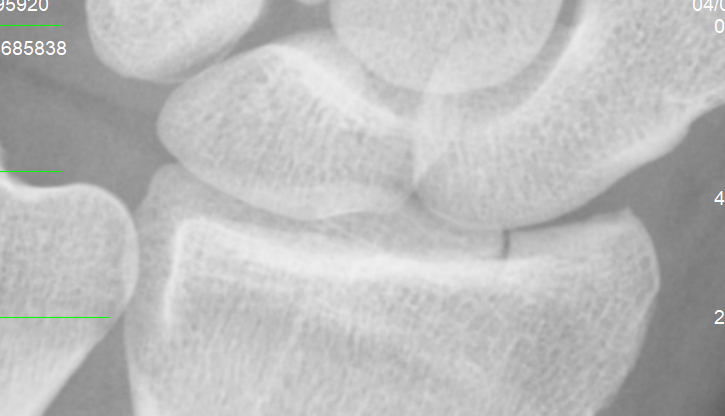

Ieri al pronto soccorso mi hanno diagnosticato frattura composta

articolare dell'epifisi distale del radio, allego immagini,

polso 1.PNG

[ 238.47 KiB | Osservato 833 volte ]